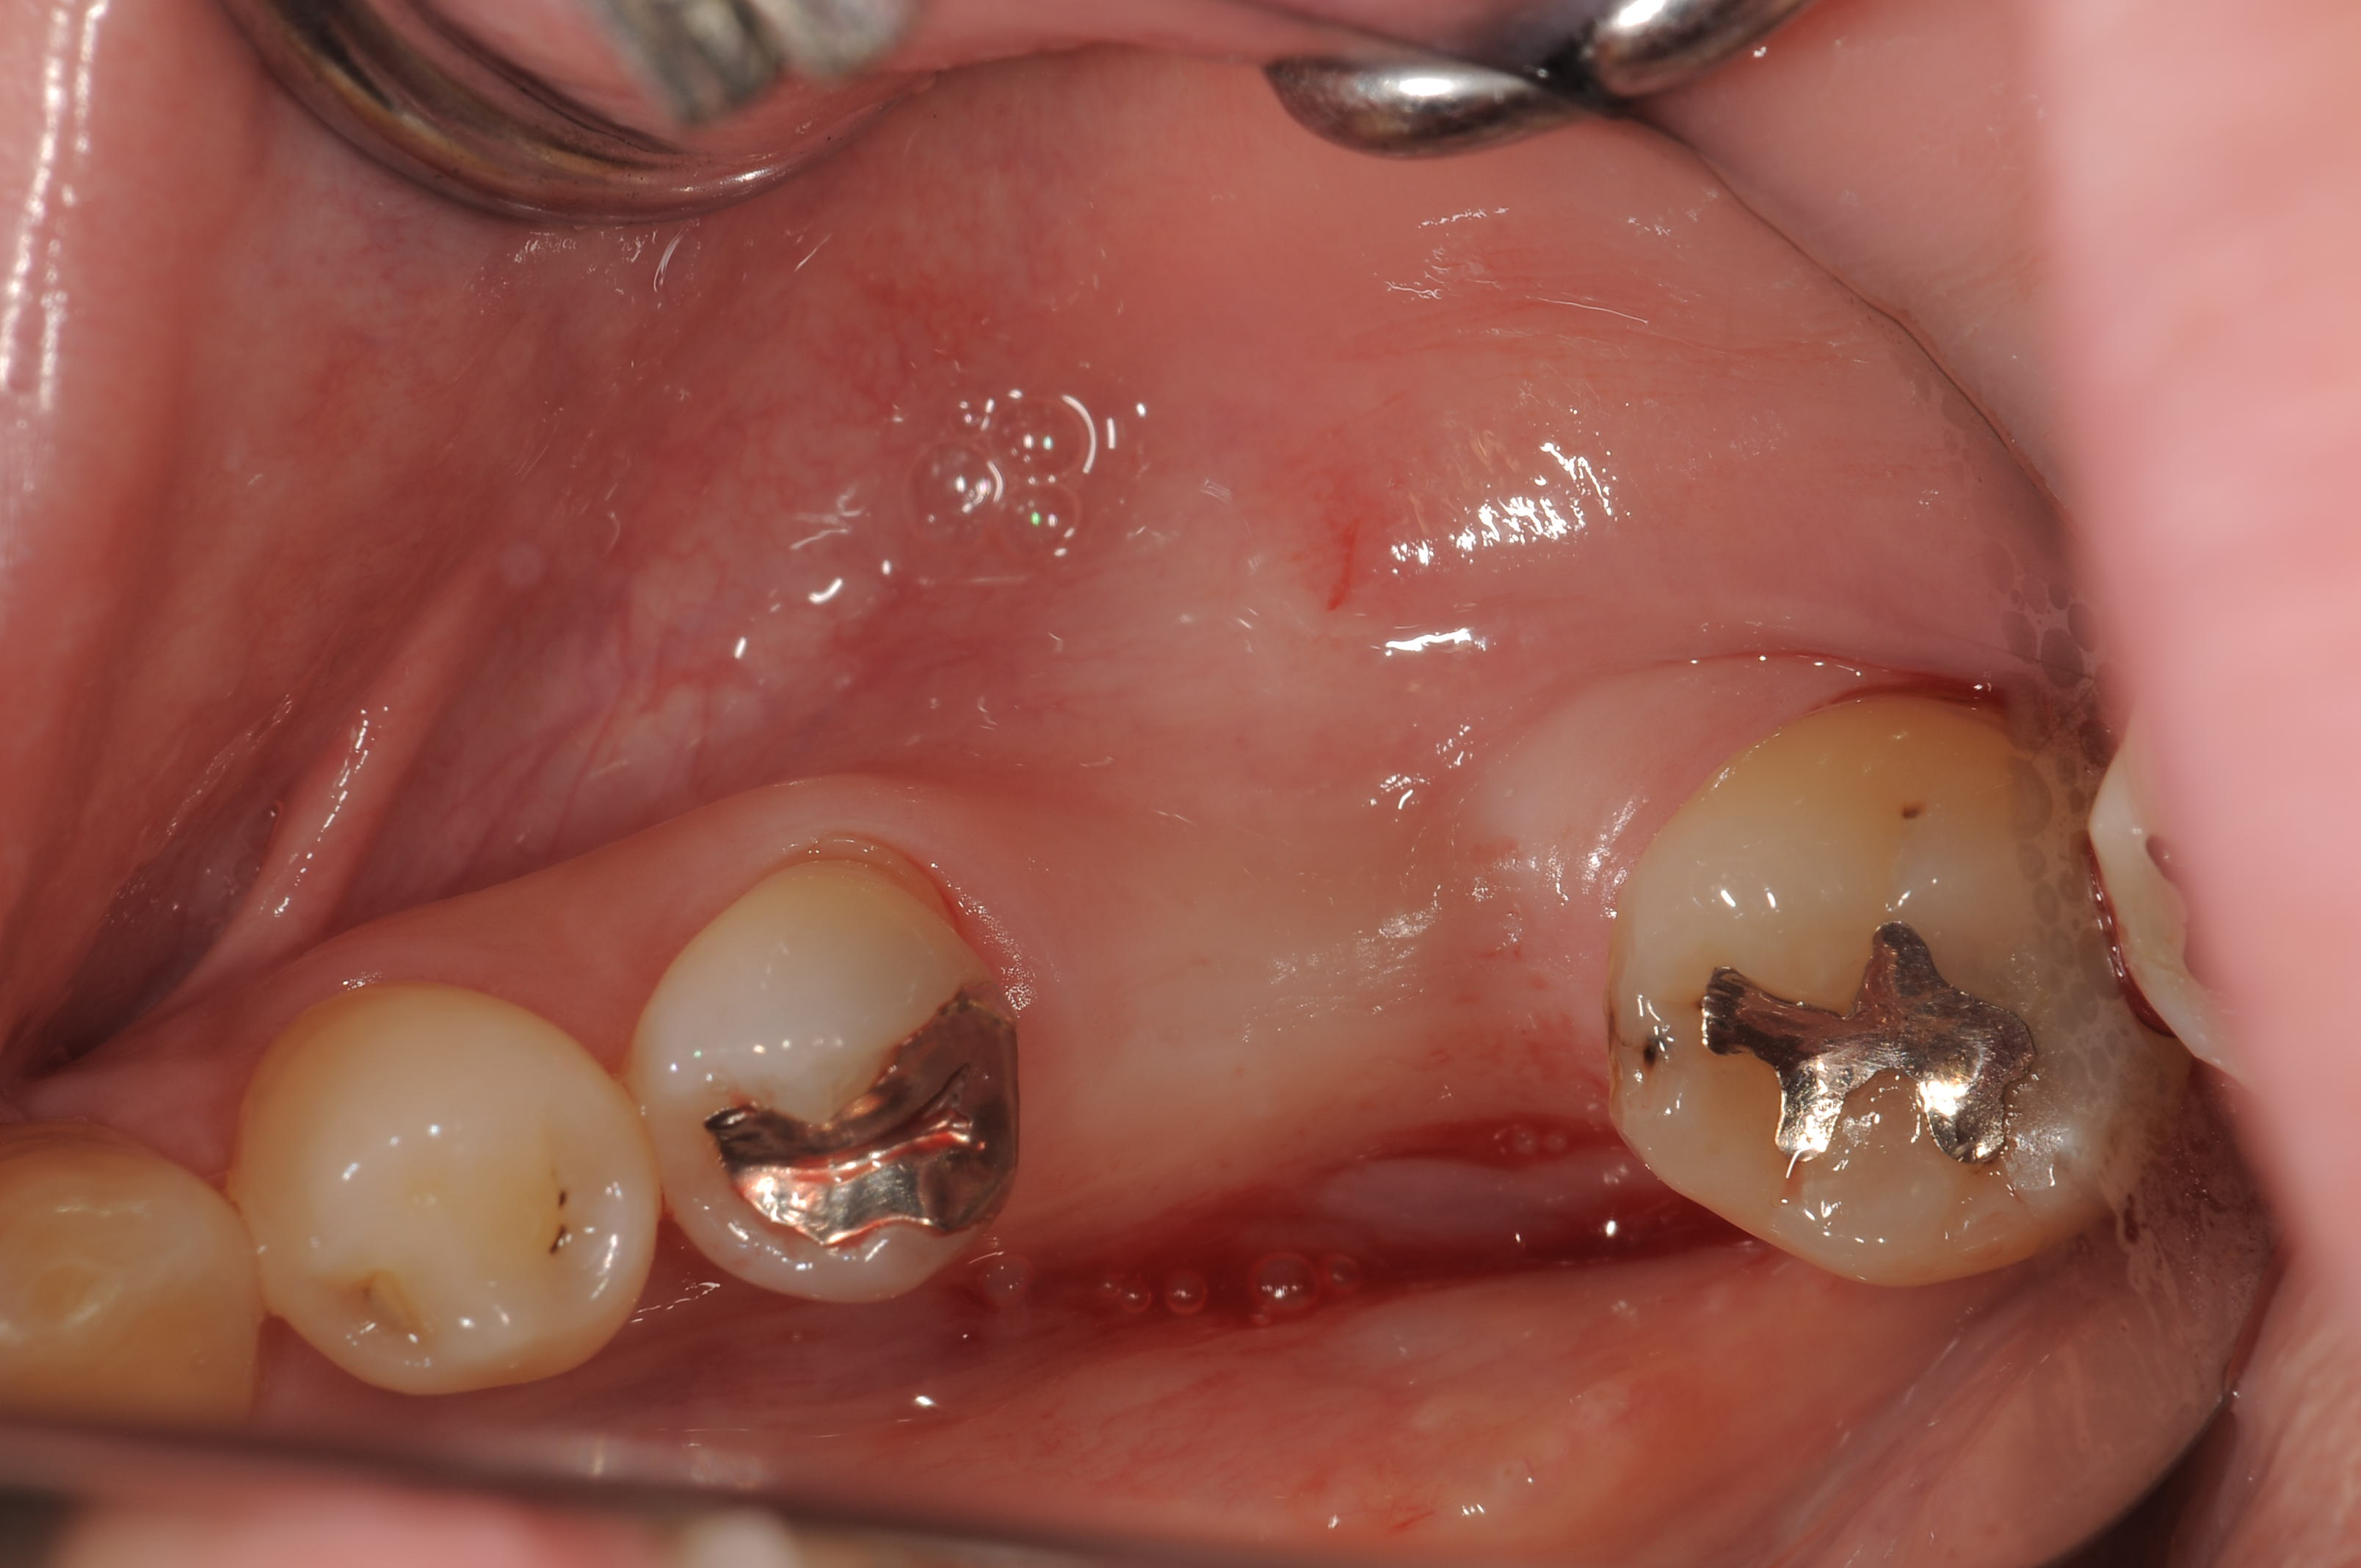

術前の埋入部位ですが、角化歯肉も十分です。